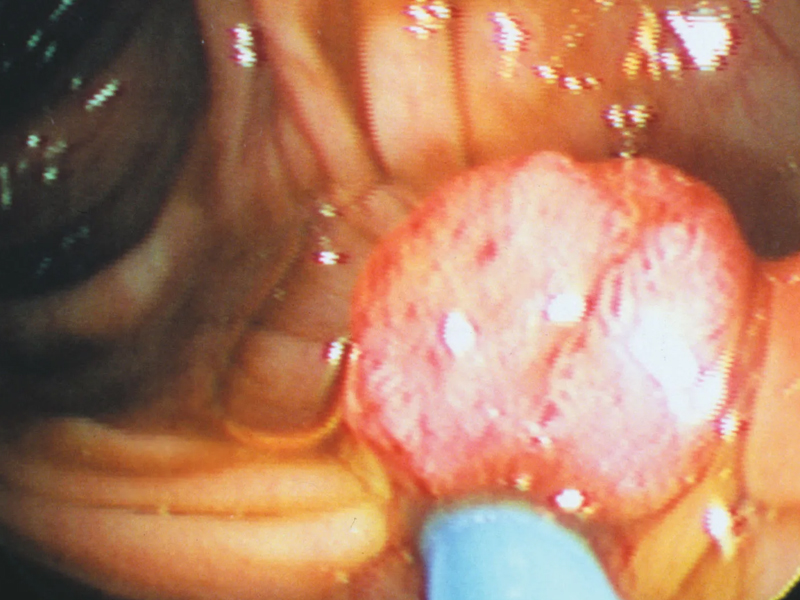

隨著發癢症狀越來越嚴重,他就到河南中醫藥大學第一附屬醫院就診。河南中醫藥大學第一附屬醫院的馬素平醫生介紹,彩超提示肝頂部有一個 19×21 毫米的佔位性病變。醫院又做了 CT 平掃和增強,以及核磁共振的平掃和增強,都進一步印證了是一個原發性肝癌。